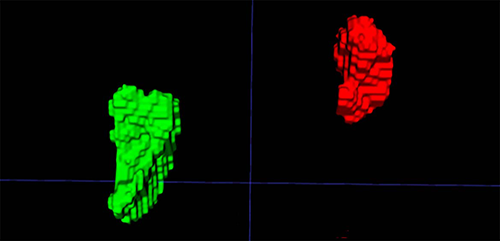

Figure 1. Left and right adrenal automated 2D and 3D segmentation in chest CT.

Figure 2. Left and right adrenal automated 3D segmentation in chest CT.